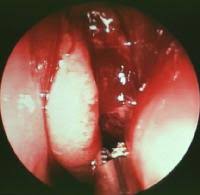

✔ Sialoendoskopi: Küçük kamera ile doğrudan kanal içine bakılarak taşın yerinin tespit edilmesi ve tedavide kullanılması için de tercih edilebilir.

Sialoendoskopi: Küçük bir kamera ve aletlerle taşın kanaldan çıkarılması

Sialoendoskopi (hem tanı hem tedavi)